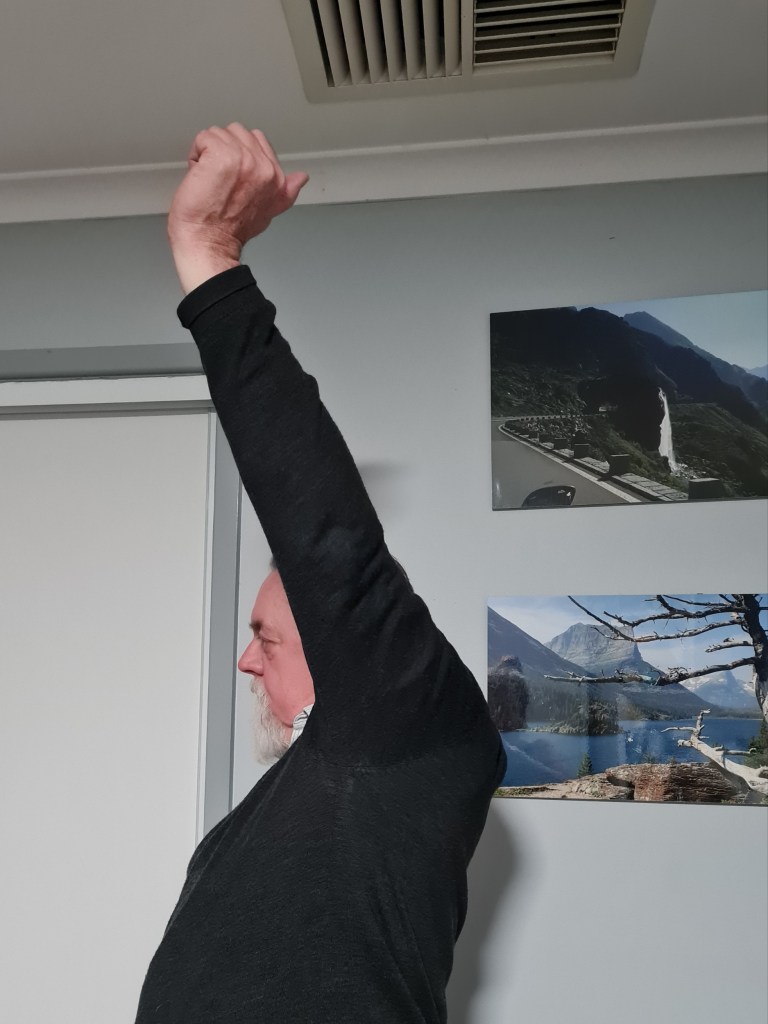

140 degrees … that’s over 40 degrees more range than I’ve had for the last 20 years with promise of more to come.

Being back on the bike seems like an appropriate and logical place to end this post. I’m off the bus and back to commuting on the bike. My physio appointment this week measured my range at over 140 degrees flexion and about 40 degrees external lateral rotation and they are expecting that should improve further over the coming months … with more hard work.